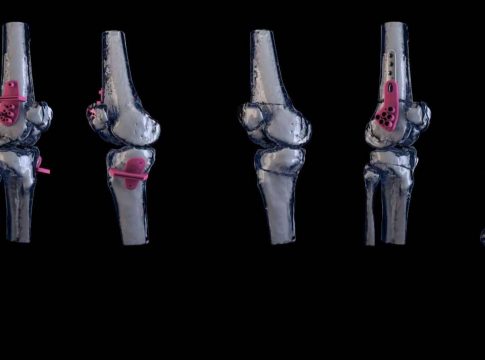

Es en este campo que nace KOOBO®, una empresa joven que cuenta en su equipo con expertos bioingenieros en el manejo de últimas tecnologías y que apuesta por el desarrollo de implantes, guías quirúrgicas y biomodelos personalizados para mejorar la calidad de vida de los pacientes, cubriendo todas las fases: desde el diseño hasta su fabricación.

Las piezas personalizadas se fabrican, utilizando las últimas tecnologías de fabricación aditiva, mecanizado de alta precisión y herramientas CAD.

Por un lado, los biomodelos personalizados permiten una planificación pre-quirúrgica más exacta. Por otro lado, se minimizan los tiempos de espera para la recepción de las piezas y el tiempo del abordaje quirúrgico, ya que no es necesario llevar a cabo una adaptación de los implantes. Consecuentemente, se reduce el riesgo de infecciones nosocomiales y se facilita el proceso de recuperación del paciente.